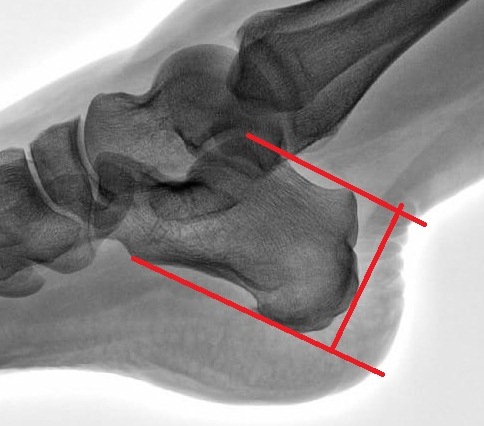

Шпора правой пяточной кости

Обратитесь к специалисту для назначения рентгеновского исследования, которое поможет точно определить наличие шпоры и ее размер.

Рентген помогает определить не только наличие шпоры, но и возможные осложнения, такие как трещины или воспаления в тканях.